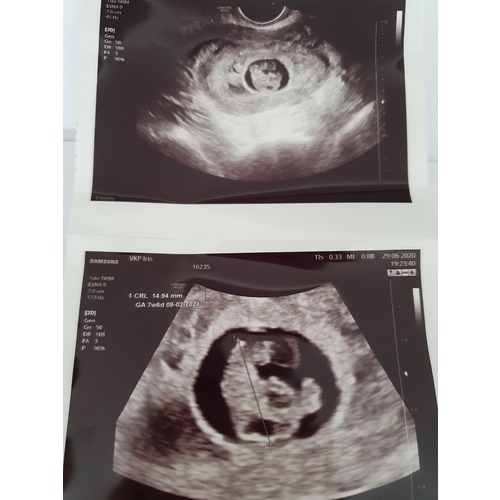

Bij mij was de vruchtzak trouwens aan de grote kant. En het gaat perfect met de baby nu 14+4 zwanger